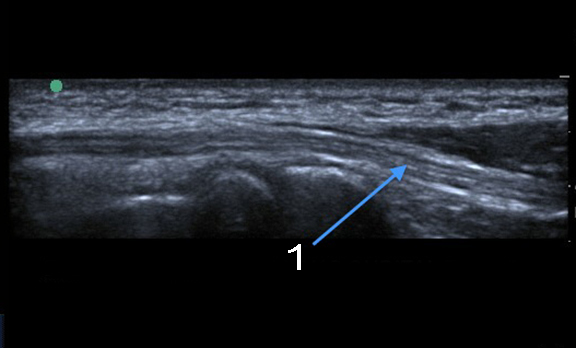

Imagen de eje longitudinal del túnel cubital del codo

Túnel largo cubital del nervio cubital